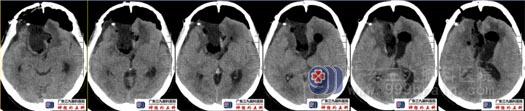

术后复查头颅CT示原肿瘤切除满意,术腔未见明显血肿形成。